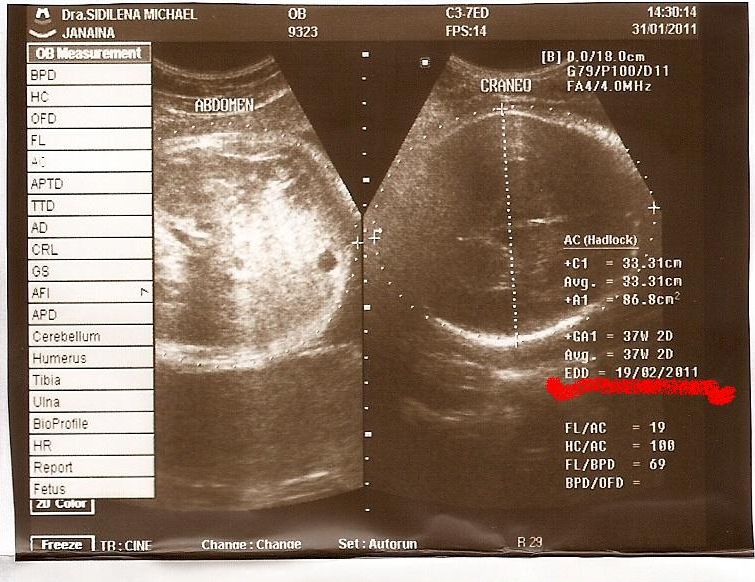

A data provável para o parto que tínhamos era dia 12/02 só que passou a tal data e nada... então me dei conta de que estava errada, a data correta seria dia 20/02, conforme o ultrassom feitos nos dias 31/01/2010 e a gente fica tão ansiosa com o nascimento próximo que acaba não se dando conta das coisas, eu nem me liguei de conferir a DPP neste ultrassom, já que desde o 1° feito em Pelotas a DPP era dia 12... os dois últimos ultrassom fizemos aqui em AG e aí a data não deu a mesma, deu diferença de 1 semana! . Pelas nossas contas ele iria nascer mesmo após o dia 27... que seria mais ou menos a data da concepção... alias alguma de vocês sabe qual é o período fértil de toda mulher??? a maioria vai responder não né...rsrs...pois é. Então vamos lá à aulinha com a tia Janah: